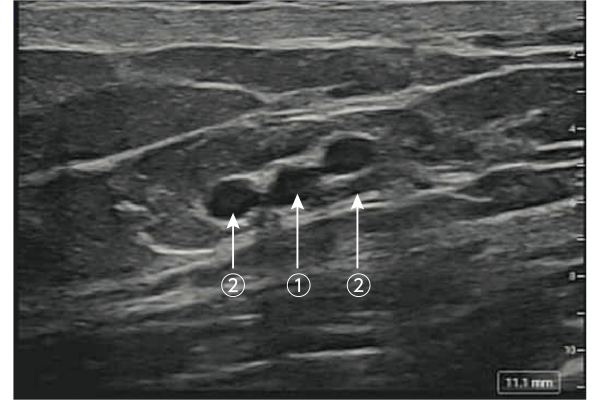

より浅層の動静脈の同定に貢献し、菲薄皮弁の拳上を効率的に支援します。

① SCIA(浅腸骨回旋動脈)0.9mm(中央)

② 伴走静脈(左右の2本)